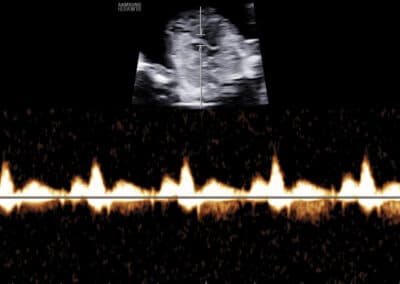

Dopplerovské vyšetření trojcípé srdeční chlopně budoucího miminka

Dopplerovské vyšetření ductus venosus

věku maminky stáří budoucího miminka srdeční frekvence u miminka velikosti NT (nuchální translucence, respektive šíjového projasnění, tzn. znamená změření množství tekutiny nahromaděné v podkoží v oblasti šíje miminka) (velikost „nuchální translucence“) koncentraci dvou hormonů v krvi maminky (free-ß-hCG & PAPP-A) přítomnosti/chybění nosní kůstky plodu normálního nebo abnormálního průtoku krve (výskytu trikuspidální regurgitace) na trojcípé srdeční chlopni miminka normálního nebo abnormálního průtoku (zvýšené hodnoty PI, tzn. indexu pulzatility) v ductus venosus miminka